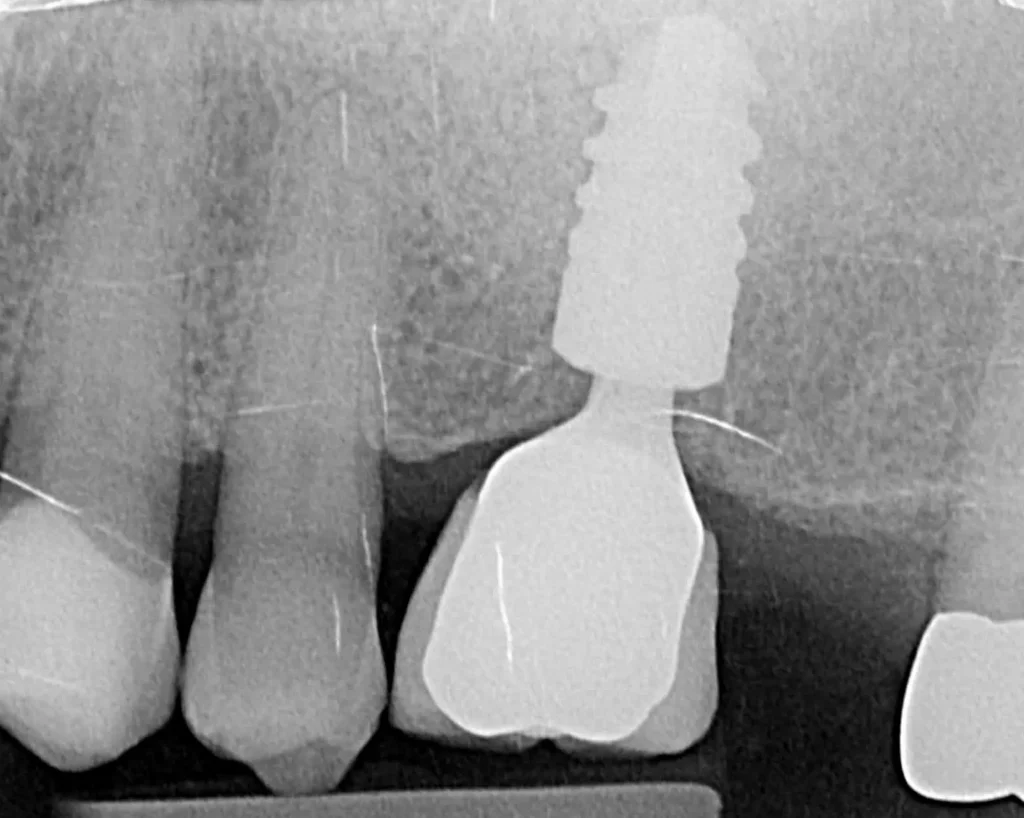

A single implant with bone grafting was placed.

Once the implant was bedded into the bone, a new porcelain crown was fitted on the implant, and a new crown was placed on the adjacent tooth to match in better.